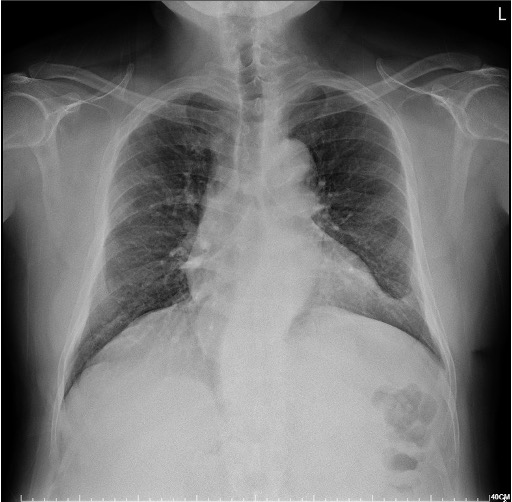

This 54-year-old male with underlying history of coronary artery disease with double vessel disease, status post percutaneous coronary intervention for right coronary artery, hypertension and hyperlipidemia for years with both under medication control. He complained of intermittent chest tightness and shortness of breath for weeks with symptoms progressively worsening. Physical examinations showed clear breathings sounds, Grade I systolic murmur at apex with regular heart beats.

Relevant Test Results Prior to Catheterization

His ECG showed sinus rhythm with old inferior myocardial infarctions. CXR showed cardiomegaly otherwise unremarkable. Transthoracic echocardiography revealed preserved LV systolic function, competent valves function and LV posterior wall hypokinesis. Thallium scan revealed ischemia for left anterior descending artery and right coronary artery.